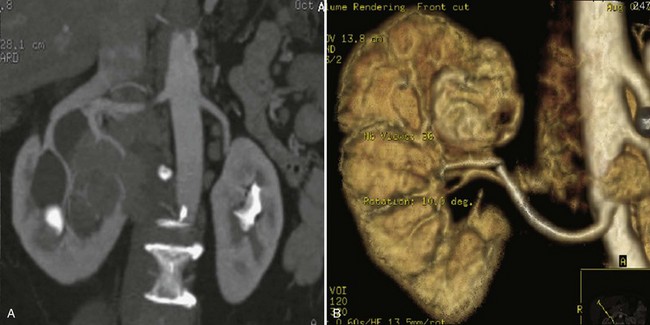

Figure 54–5 Arterial anatomy can be well defined using CT (A) and three-dimensional reconstruction (B).

Figure 54–11 Horseshoe kidney with multiple arterial branches well defined with three-dimensional imaging.